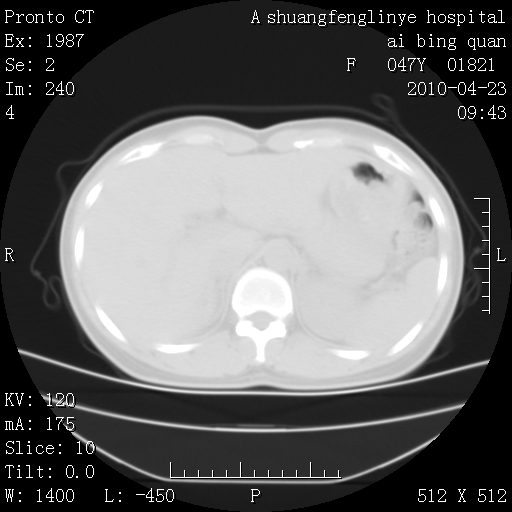

标题: CT25944:胸痛、气短、前几日高烧!肺Ca?请会诊! [打印本页]

标题: CT25944:胸痛、气短、前几日高烧!肺Ca?请会诊!

双肺多发结节,考虑转移瘤,肺癌肺转移不除外

周围型肺癌并肺转移

双肺多发结节,部分密度较高,最大结节边缘光滑。临床有“胸痛、气短、前几日高烧”病史。首选考虑:右肺感染性病变!建议积极消炎后复查!

建议抗炎治疗后复查,排除肿瘤性病变。